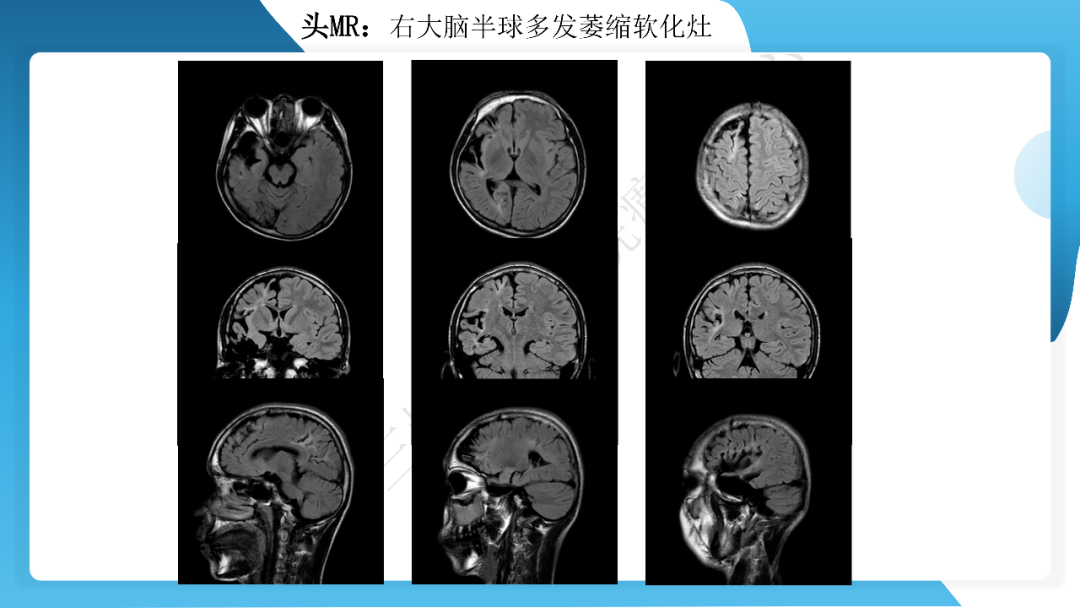

《「痫停」信步》癫痫治疗病例荟萃第三十五期---胼胝体全段切开治疗难治性癫痫 1 例